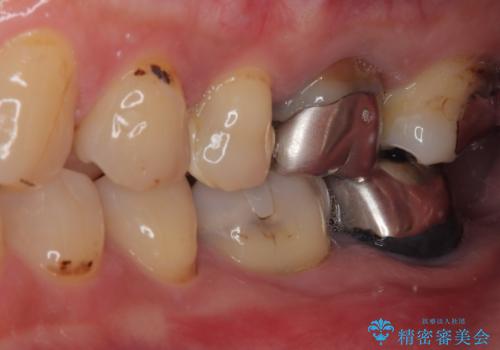

- 下顎大臼歯が噛めないほどの痛みを感じるとのことで来院された患者様です。

レントゲン写真などで診査を行ったところ、不適合な詰め物の周りから炎症が波及し、神経組織が壊死していると診断されました。

まずは根管治療を行い、症状が消退したことを確認してオールセラミッククラウンにて補綴治療を行うこととしました。